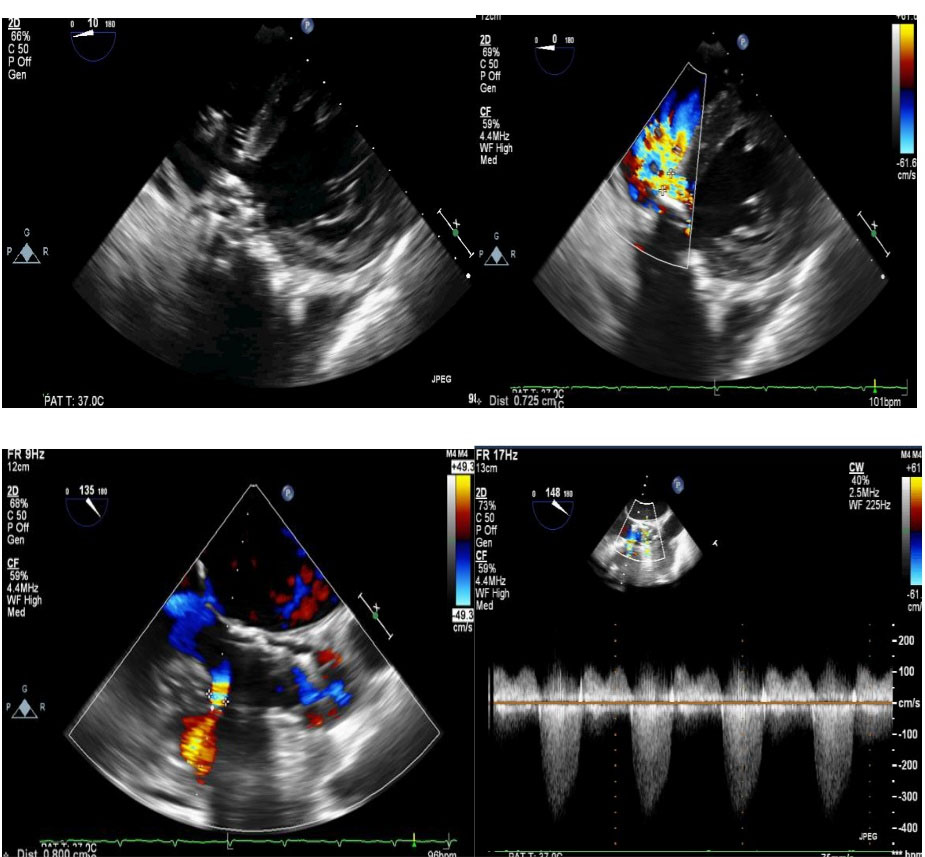

Figure 5.

Transesophageal and transthoracic images of the VSD muscular device after the closure of the ventricular septal defect.

The patient was an active 82-year-old woman (NYHA IV) with shortness of breath at rest. Her comorbidities included hypertension and asthma history. During her examination, she was found to have normal left ventricular (LV) systolic function (ejection fraction; 60%) and severe calcific aortic valve stenosis (aortic valve area: 0.7 cm2; peak / mean gradient: 85/55 mm Hg) on transthoracic echocardiography (TTE). Coronary angiography was found to have normal coronary vessels. The patient with 5.1% STS score was decided to undergo TAVI by our Heart Team. On multi-slice cardiac computed tomography (CT), severe calcification from the aortic valve level and calcified nodule towards the LVOT were noted. Calcific nodule extending to LVOT shown in . The procedure was briefly performed as follows: A 6-F sheath was placed in the right common femoral artery and vein then proglide was inserted. A stiff wire was then inserted through a pig tail catheter. 19 F delivery catheter has been advanced from descending aorta. By performing fast pacing, a nucleus 20×40 mm balloon was predilated and a self-expandable 29 mm Portico prosthesis was implanted. At this stage, there was second grade aortic ınsufficiency (AR) and the prosthesis was postdilated with nucleus 25×40 mm balloon. After the procedure, a very good result was obtained with only minimal insufficiency and elimination of the aortic gradient. No problem developed during the follow-up during hospitalization and no obvious pathology was detected in the post-procedure follow-up echocardiography. However, a pansystolic murmur was detected in the physical examination of the patient with dyspnea at the follow-up 1 month later, and aortic Portico prosthesis (maximum gradient:11 mm Hg, minimal insufficiency) was detected on TTE. However, the right chambers were dilated with significant tricuspid regurgitation and an increased systolic pulmonary artery pressure of 60 mm Hg. In addition, a perimembranous VSD 7 mm was evident beginning from the edge of the prostetic valve, resulting in a significant left-to-right shunt. Based on these findings , it was decided to perform interventional treatment of the defect using the Amplatzer muscular VSD occluder. Right femoral artery and vein canulated using 6-F sheath. A pigtail catheter was passed to the LV. A 0.035 hydrophilic wire and 5-F JR-3.5 catheter were then passed through the VSD to the RV. The wire unintentionally went into the inferior vena cava and the catheter sent over the wire to the inferior vena cava. Then the hidrofilic wire was exchanged with a 0.035 300 cm Noodle wire. The wire was snared in the inferior vena cava and externalized through the right femoral vein. From the right femoral vein a 7-f delivery sheath sent to the ascending aorta through inferior vena cava and the VSD. VSD diameter was measured 7 mm by ventriculography and 8 mm with TOE. Later, 10 mm Amplatzer muscular VSD occluder device was sent through the long sheath, and the first disc was opened in the ascending aorta. Then the system was pulled back to the VSD and the second disc was unsheated (). On 3D-TOE the occluder device was in a correct position, and there was a minimal shunt possibly through the occluder device (). It was disconnected from the delivery cable after confirming that there was no compression or problem with the aortic valve. Two days after the procedure, the device was in a good position, there was mild tricuspid regurgitation and systolic pulmonary artery pressure was 40 mmHg (). After one week of follow-up, the patient was discharged home. It continues to be active with significant improvement in shortness of breath (NYHA I-II) twelve months after the procedure.